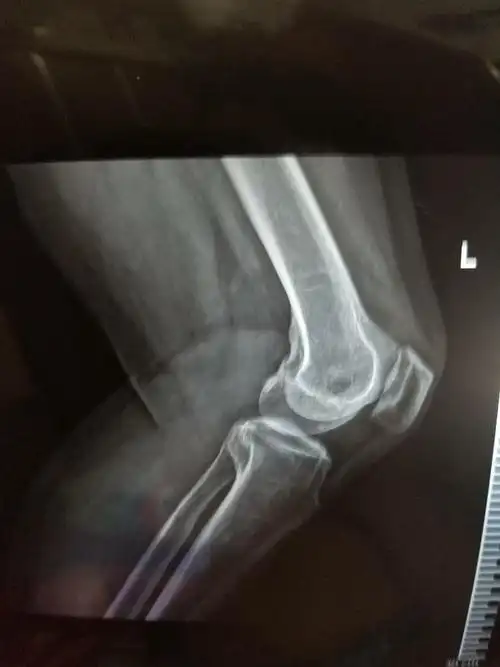

膝盖上有一块突出的地方 那是骨刺吗?

膝关节骨刺处理

膝盖骨刺最有效的办法解析膝关节长骨刺怎么治疗

膝盖骨刺,骨质增生

问:请问我这膝盖骨头长刺的情况严重么?

膝关节长骨刺行走困难?昆明骨科医院微创"拔刺"